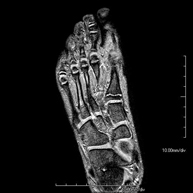

Exploración para el estudio de la articulación y sus frecuentes lesiones de ligamentos (esguinces) así como de la afectación de otras estructuras como el cartílago o el hueso. También es de gran utilidad para diagnosticar alteraciones en el tendón de Aquiles (tendinitis, roturas). Duración de aproximadamente 20 minutos. No emplea radiación ionizante. - RM Pie

Exploración para el estudio de lesiones en tendones músculos y pequeñas articulaciones. Permite valorar con eficacia las lesiones en el cartílago. También es de mucha utilidad para completar la exploración ecográfica previa. No emplea radiación ionizante. Tiene una duración aproximada de 20 minutos. - Artro-RM Hombro